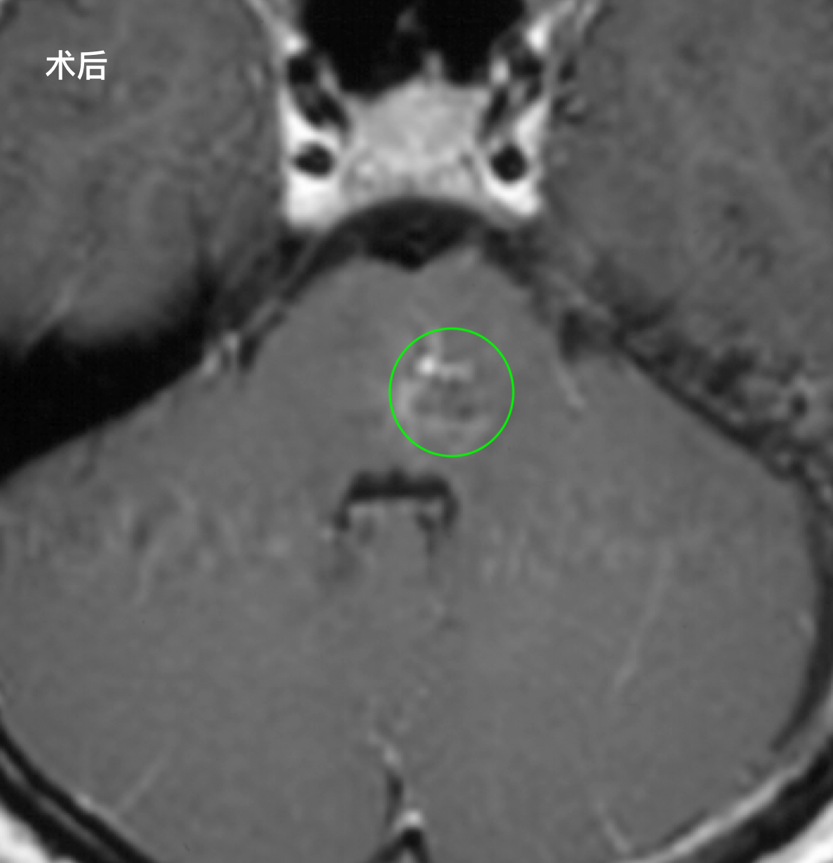

术后恢复进程顺利超出预期。手术当天宋同学在ICU平稳度过;次日复查CT未见新发出血,成功转入普通病房;第三天,困扰她已久的视物重影和肢体无力症状便已明显减轻;到第十天,她已经能够自主站立行走,并顺利办理出院手续。

而更令人感慨的奇迹,发生在此后的三年里。曾经在生死边缘徘徊的这位少女,神经系统功能完全恢复如初,并以优异的成绩通过了德国高考,收到了心仪大学的录取通知书。那段与死神擦肩而过的经历,最终化作她继续前行的力量,让她的人生在劫后的阳光里重新铺展开来。